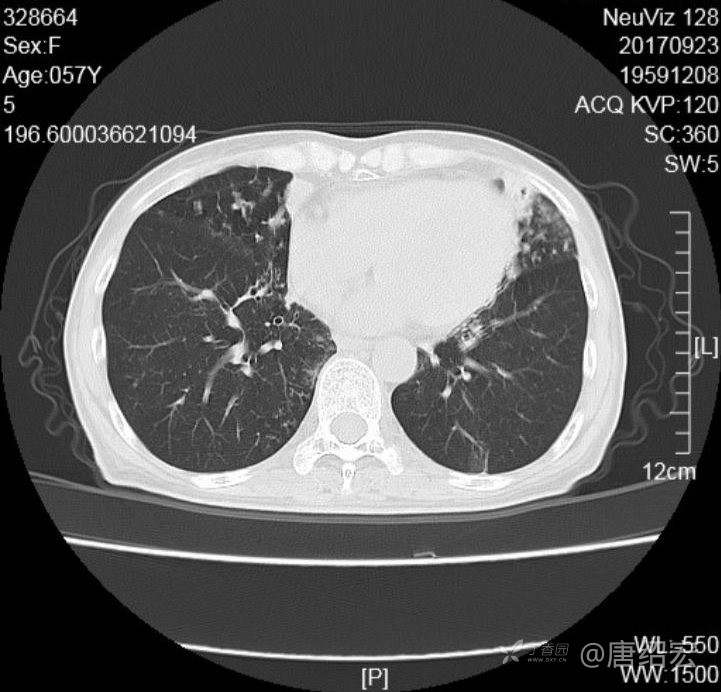

中年女性满肺树芽征还有支气管扩张,考虑什么疾病?

女,57岁,

主诉:发热、咳嗽、咯黄痰,胸闷3天入院。